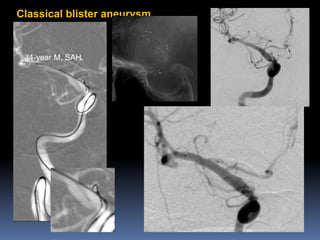

Classical blister aneurysm

34-year M, SAH